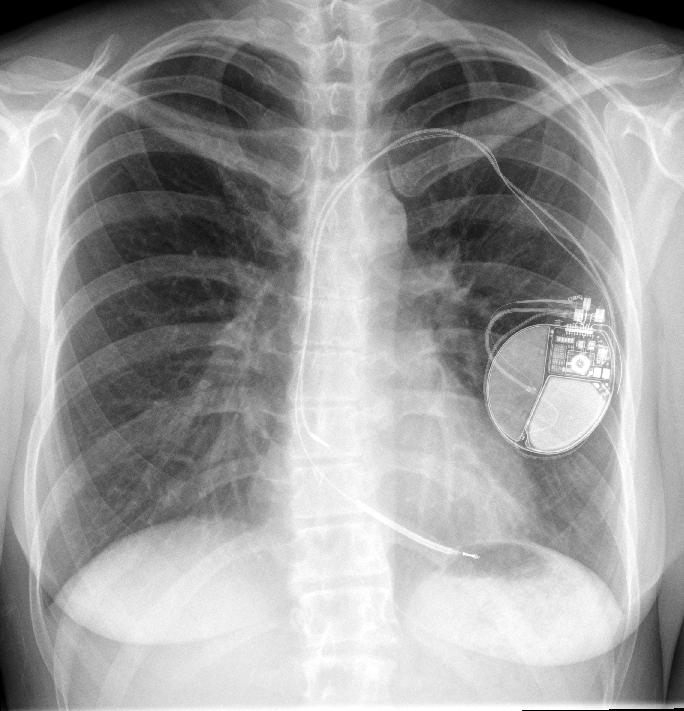

Paul Wylie Heart Attack. Wylie, right, in the hospital with his friend billy griggs, “hard hat,” who performed cardiopulmonary resuscitation until the ambulance came. Paul wylie was an olympic athlete. Paul wylie is back on the ice after suffering sudden cardiac arrest in april, a condition that has a survival rate of only 10. Three years ago, figure skating olympian paul wylie overcame a substantial disadvantage and survived sudden cardiac. But sudden cardiac arrest doesn't discriminate. Paul wylie, the 1992 olympic figure skating silver medalist, said he survived his sudden cardiac arrest april. Meanwhile, my wife kate was in bed at home. Paul wylie, a 1992 olympic figure skating silver medalist, suffered a heart problem tuesday, according to his wife, kate. Thanks to quick care at an atrium health hospital and a new icd device implanted by his physicians at sanger heart & vascular institute, wylie has a second chance at life. Paul wylie said he was “doing much better” but still hospitalized following a sudden cardiac arrest last tuesday, according to a.

Wylie, right, in the hospital with his friend billy griggs, “hard hat,” who performed cardiopulmonary resuscitation until the ambulance came. Paul wylie is back on the ice after suffering sudden cardiac arrest in april, a condition that has a survival rate of only 10. Meanwhile, my wife kate was in bed at home. Thanks to quick care at an atrium health hospital and a new icd device implanted by his physicians at sanger heart & vascular institute, wylie has a second chance at life. Paul wylie, a 1992 olympic figure skating silver medalist, suffered a heart problem tuesday, according to his wife, kate. But sudden cardiac arrest doesn't discriminate. Paul wylie said he was “doing much better” but still hospitalized following a sudden cardiac arrest last tuesday, according to a. Three years ago, figure skating olympian paul wylie overcame a substantial disadvantage and survived sudden cardiac. Paul wylie, the 1992 olympic figure skating silver medalist, said he survived his sudden cardiac arrest april. Paul wylie was an olympic athlete.